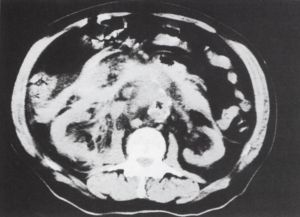

1. ábra.

A vese hilusok síkjában, az aorta falában lévő meszesedés megszakad - ez a ruptura helye, az aortától jobbra, ventralisan magas denzitású képlet, haematoma látszik. A jobb vese előtt a retroperitoneum beszűrt.

2. ábra.

Az 1. ábrával megegyező síkban, kontrasztanyag adása után készült felvétel, a kontrasztanyag egy része az aorta előtt látszik.